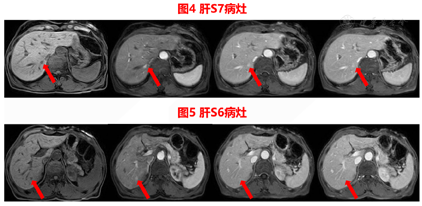

胆囊切除术前CT检查发现肝内病灶,胆囊切除术中病理结果证实S4段病灶为神经内分泌瘤,胆囊切除术后MRI确定剩余病灶,US-MRI容积导航影像融合联合超声造影进行病灶定位、引导、术后评估。

结合胃肠镜等检查及实验室指标,初步考虑肝原发性神经内分泌瘤并肝转移,由于患者过分焦虑,且拒绝手术切除,经多学科会诊后拟在超声US-MRI容积导航影像融合引导下经皮肝肿瘤微波消融治疗。

患者在2020年9月3日送手术室在复合麻醉下行US-MRI容积导航影像融合引导下经皮肝肿瘤微波消融治疗,见图8,图9。

US-CT/MRI影像融合容积导航技术结合了超声和CT/MRI的优点,同时避免了它们的缺点,这是一种可以在同一设置上同时显示超声和CT/MRI图像的技术。通常通过使用磁导航系统来实现,该系统允许协调两种不同的成像模式并允许它们在同一屏幕上显示。在位置感测单元的帮助下,CT/MRI图像随超声图像移动。在两个图像匹配良好之后,可以根据CT/MRI图像定位超声图像上的目标病变。将CT及MRI良好的空间分辨力与超声可实时动态显像的优点相结合,能够实现对病灶的精准定位,特别对常规超声显示困难的病灶,US-CT/MRI影像融合磁导航技术显示出良好优越性[6,7]。

本例患者在常规超声未发现异常病灶,于是在融合成像辅助定位下,对磁共振对应区域进行超声造影,确定了病灶位置,进行消融及术后即时评估。术后患者规律复查,消融效果良好,病灶未见活性。